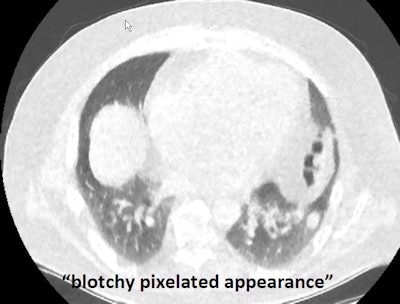

But no matter how good the reconstruction scheme, ultralow-dose imaging acquisition might be challenged in areas such as near the shoulders, where thicker, denser tissues could potentially create more localized noise and obscure visualization of the lungs, she said. Readers have also noted the blotchy, pixelated appearance of MBIR scans that might make them difficult to read.

"Despite this blotchy, plastic-y, different sort of look to the lung tissue, we can still see quite small pulmonary nodules ... it's just not the pretty picture of yesteryear," she said.

In addition, despite the blotchy, pixelated appearance, almost all images were of diagnostic quality, similar to the standard low-dose technique. However, the study did not report on nodule detection.

The ultralow-dose images were blotchy and pixelated, "however, the performance of [ultralow-dose] MBIR was significantly superior to that of [ultralow-dose] FBP for the detection of noncalcified pulmonary nodules" (p = 0.002) and did not significantly affect screening CT results, according to Yamada and colleagues.